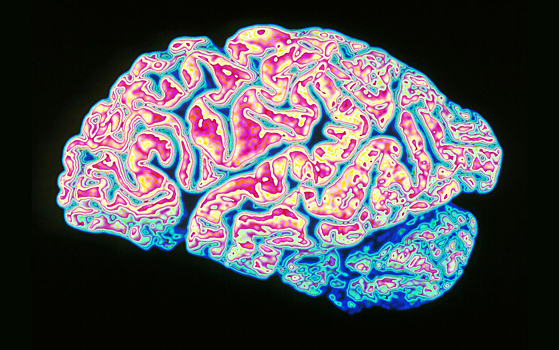

Известно, что при рассеянном склерозе лимфоциты — клетки иммунной системы — атакуют нейроны и вызывают демиелинизацию, то есть повреждение миелиновой оболочки нервных волокон центральной нервной системы. Обычно эти клетки активируются при взаимодействии с чужеродными фрагментами белков (антигенами), но при рассеянном склерозе действуют аномально. Однако раньше ученые не могли выяснить, на какую же молекулу так реагируют лимфоциты.

В новой работе ученые из Швейцарии, США и Испании изучали Т-лимфоциты пациента, который умер от рассеянного склероза. Они протестировали действие Т-лимфоцитов на 200 смесях потенциальных антигенов, каждая из которых содержала 300 миллиардов вариантов. Два вещества, вызывающие наиболее сильную реакцию, оказались участками человеческого фермента гуанозиндифосфат-L-фукоз синтаза (GDP-l-fucose synthase), который участвует во многих процессах, начиная от формирования памяти до определения группы крови. Дополнительно ученые протестировали клетки 31 пациента с ранними симптомами или диагностированным рассеянным склерозом. В 12 случаев Т-лимфоциты также реагировали на этот фермент.

В мозге находится достаточно много этого соединения, но никто раньше не подозревал о том, что оно связано с рассеянным склерозом. На основе открытия можно разработать методы лечения, как минимум облегчающие симптомы болезни, такие как онемение и мышечная слабость. Такая терапия будет по механизму действия напоминать аллерген-специфическую иммунотерапию, которую используют для борьбы с аллергиями. Авторы планируют начать первые испытания лечения в следующем году.